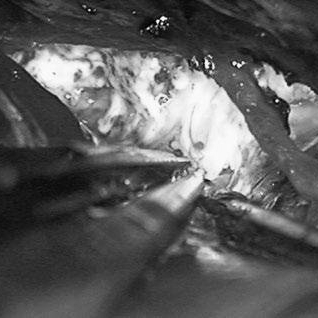

羅頓教授團隊為他進(jìn)行了半側(cè)顱骨切除術(shù),也就是給大腦“掀開”一塊顱骨,造個“臨時天窗”,讓腫脹的腦組織先“喘口氣”。

隨后血管造影顯示右側(cè)胼周動脈上鼓著個“氣球”(動脈瘤),旁邊還盤著一團亂麻似的血管(AVM),AVM由雙側(cè)PcaA供血,引流向前MedFrV和SplenV。這哪是血管?簡直是“交通癱瘓的立交橋”!

需要同時處理動脈瘤和AVM,通過雙側(cè)開顱并排夾閉動脈瘤,徹底斷了“炸彈”的“氣源”;然后切開動脈瘤使之縮小,原本像氣球一樣鼓的動脈瘤瞬間變“癟”。